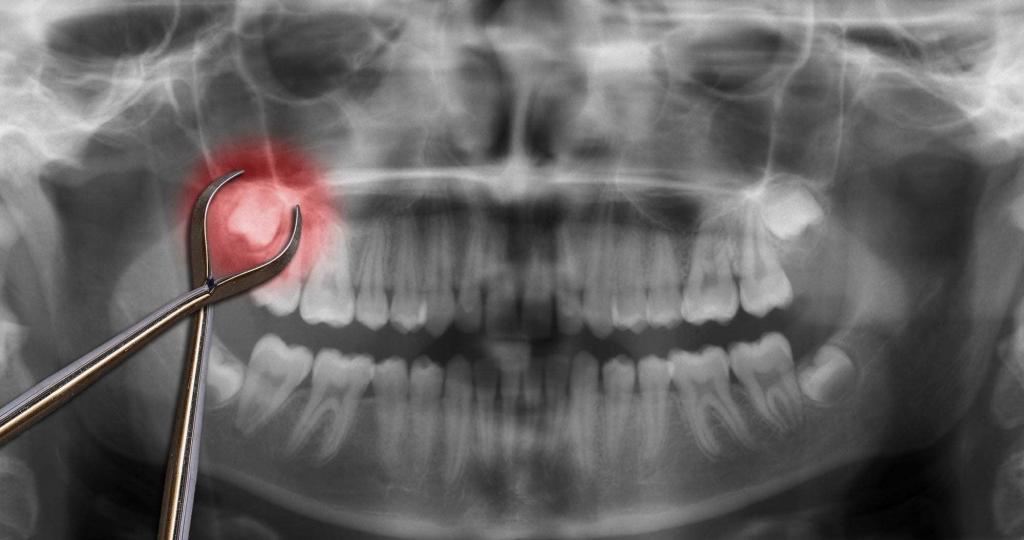

During a tooth extraction, the tooth is removed from its socket in the bone. Your dentist will decide which method of extraction to use based on the location of your tooth.

If your tooth has not erupted (i.e., come through the gum line) or has broken off at the gum line, a more complex procedure known as a surgical extraction will be necessary. Your dentist will refer you to an oral surgeon, who will make a small incision in the gums to surgically remove the broken, decaying, or impacted tooth.